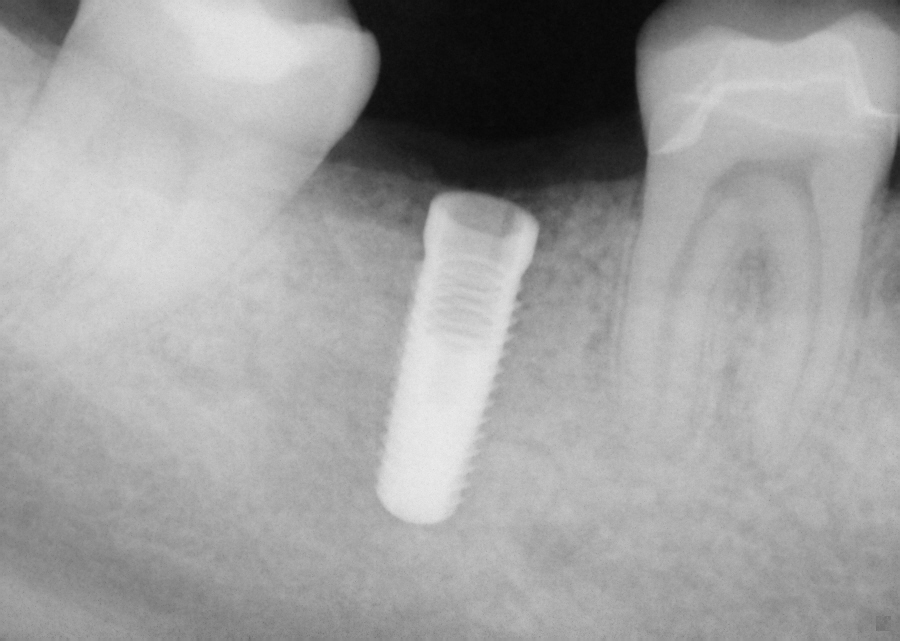

This implant was initially placed at the crest of the ridge in 2012. its placement did not allow proper emergence profile and subsequently lost bone around the head of the implant by 2015. The lack of blood flow to the crest of the bone at the cortical plate certainly could have contributed to its demise. By 2015, the bacteria trap forced a new restoration to be placed which also ultimately lead to chronic inflammation due to improper contours. The implant itself was well integrated and the decision was made to remove the top 3-5 mm of the implant and treat it as a cast post and core.